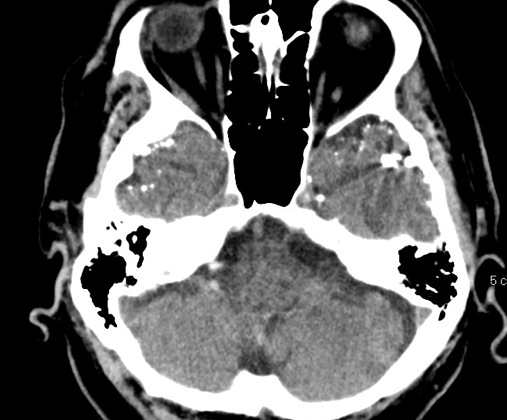

Figure 3 for case Lipiodol droplets after myelogram

Figure 3